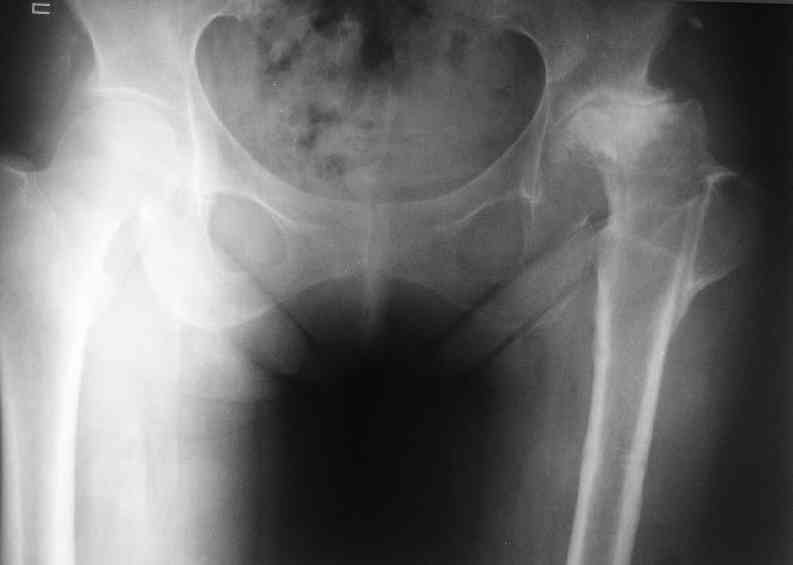

Еще пара фото, ситуация несколько иная, задачи те же, открытое вправление застарелого вывиха в 2002, молодой возраст. Сейчас госпитализирована для эндопротезирования.

Коллеги, обещанный follow-up.

Больного прооперировали на прошлой неделе (цементный протез, цемент с гентамицином). Использовали задне-боковой доступ. В области перелома подвижности практически не было, так что тему сообщения уместно заменить на "неправильно сросшаяся шейка". И в головке, и во впадине

были значительные дегенеративные изменения, так что ни биполяр, ни остеосинтез тут неуместны (хотя это предлагали в ortopod'е). После релиза удлинили ногу на 3 см. Дальше удлинять побоялись из-за

натяжения седалищного нерва, хотя в принципе можно было бы еще 15-20 мм нарастить. По послеоперационной рентгенограмме анатомическое укорочение порядка 15 мм. Клинически при ходьбе - 4 см, но это за счет перекоса таза.

The patient underwent cemented THR on last week. Postero-lateral approach was used. There was only minimal motion at the fracture site and we had to cut the femoral head with oscillating saw. The femoral head was deformed with it's cartilage completely absent in some areas.

Acetabulum showed gross degenerative changes, especially in superior rim. So I think it was right choice not to do ORIF in this case. After some soft tissue release we've lengthened the leg up to 3 cm. Further lengthening was possible but we stopped at that moment due to tension of n. ischiadicus. Now patient walks with crutches. Leg length discrepancy is about 4 cm due to pelvic tilt (discrepancy on post-op x-ray is 15 mm).